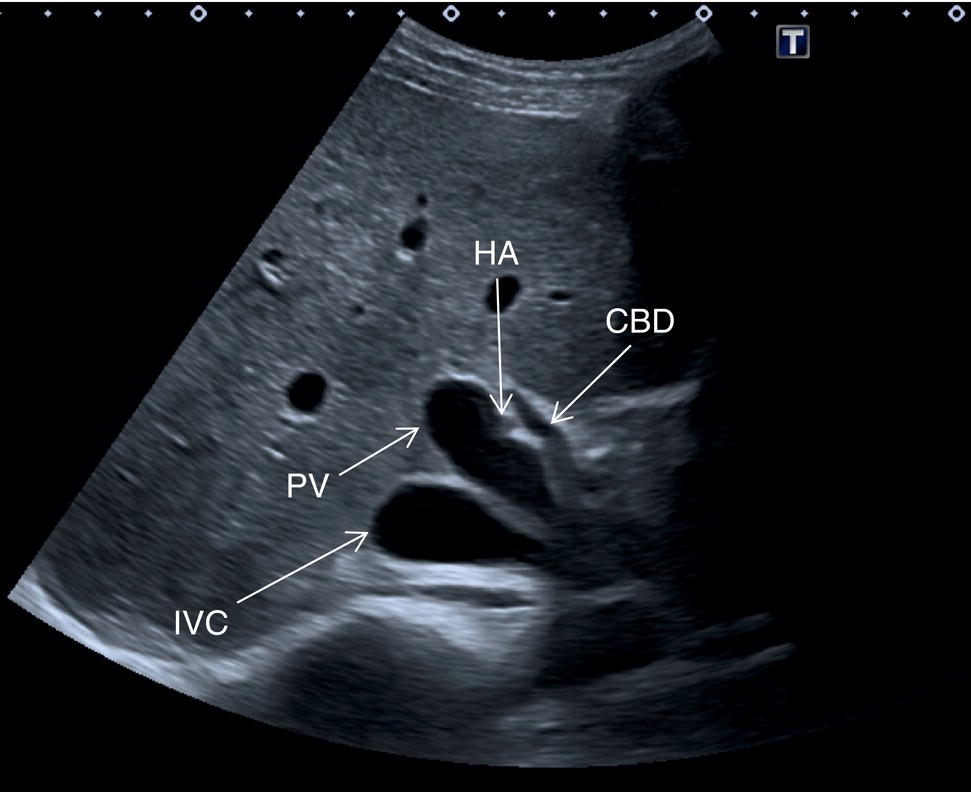

Other anatomical variants include the position of the PV, HA, and CBD at the level of the hepatic hilum. In the majority of cases the PV lies posteriorly, and the HA lies between the PV and the above CBD, while less frequently the HA will run above the CBD (Figure 3.20) or below the PV. The main trunk of the PV usually bifurcates at the porta hepatis into a main left and right branch and a further anterior and posterior branch of the right trunk. Alternatively the PV might have a trifurcation that might be extrahepatic or intrahepatic. The hepatic veins can also show some anatomical variants. With regard to the RHV, this is usually single and dominant, while in a minority of cases there might be an early bifurcation or trifurcation or multiple small RHVs entering the IVC. The most common variant is an accessory right inferior hepatic vein. Both the MHV and LHV can be double and sometimes form a common trunk that drains independently into the IVC. When the hepatic veins are duplicated, typically the larger is used for segment classification. The caudate lobe might have a single vein or several small hepatic veins that drain independently and directly into the IVC. The HA can have several anatomical variants, especially with regard to its origin. The most common is directly from the aorta or the superior mesenteric artery. All these vascular variants do not have pathological implications, but should be kept in mind since they have important technical implications in a case of liver transplant, resection, or embolic treatment of liver tumours [7]. Rare vascular anatomical variants include congenital portal venous shunting (see Chapter 11).

The GB is assessed in the subcostal position, in two orthogonal planes, and also intercostally. As a first approach, place the transducer on the anterior abdominal wall along the mid‐clavicular line, adjusting its position until the GB is located. Ask the patient to take a deep breath to lower the diaphragm and push the liver downwards below the costal margin; this will facilitate GB visualisation. It is essential to image the GB in its entire long axis and to angle the transducer so that it is also imaged transversally. The longitudinal intercostal approach will complete the GB visualisation, also offering an alternative to a sometimes challenging subcostal view in case of bowel gas interposition (Figure 3.27) (Video 3.9). In other circumstances, especially in the presence of narrow intercostal spaces, an intercostal approach might not be ideal. The CBD is best visualised with the patient supine or slightly turned with the left side down. Start with the probe obliquely positioned in the epigastrium, in line with the anatomical plane of the CBD. Sweep subcostally and outwards until you see the image of the portal triad (Figure 3.28). This may require some fine adjustments of the probe position (Video 3.10). The CBD is usually measured longitudinally where the HA intersects the CBD and PV; nevertheless, if the CBD shows some size variations it should be measured at the level of its maximal calibre (Figure 3.29). As for the GB, there may be occasions, owing to bowel gas, in which the CBD is better visualised in the anterior intercostal plane (Figure 3.30). ![]()

The HA has echogenic walls, it runs anteriorly to the PV and posteriorly to the CBD, and its normal calibre at the hepatic hilum measures up to 3 mm in diameter (Figure 3.34). The hepatic veins have thinner and less echogenic walls [8] and have a straighter and linear course compared to the portal venous system. Although the measurement of the hepatic veins is usually not performed on a routine basis, the cut‐off value of their calibre is approximately 8 mm, measured at about 2–3 cm from their confluence into the IVC [9]. It should be kept in mind that in lean subjects both IVC and hepatic veins may be more ectatic. When performing a liver ultrasound scan it is important to keep in mind that the echogenicity of both hepatic veins and PV walls changes according to the angle between the ultrasound beam and the vascular wall. The more acute is the angle of insonation, the closer it is to being parallel to the longitudinal axis of the vessel. Therefore, despite there being clear differences between the thick perivascular collagen of the portal venous system and the thin walls of the hepatic veins (Figure 3.35), if the angle of insonation is low between the ultrasound beam and the PV walls, these could appear very thin or even not be visible. On the other hand, if the angle of insonation with the hepatic veins is close to 90°, the walls will appear thick and echogenic. It is always important to keep in mind this physical principle, remembering the anatomical landmarks and tracing the vessels to their origin: the PV to the hepatic hilum and the hepatic veins to their confluence into the IVC.

Other anatomical variants include the position of the PV, HA, and CBD at the level of the hepatic hilum. In the majority of cases the PV lies posteriorly, and the HA lies between the PV and the above CBD, while less frequently the HA will run above the CBD (Figure 3.20